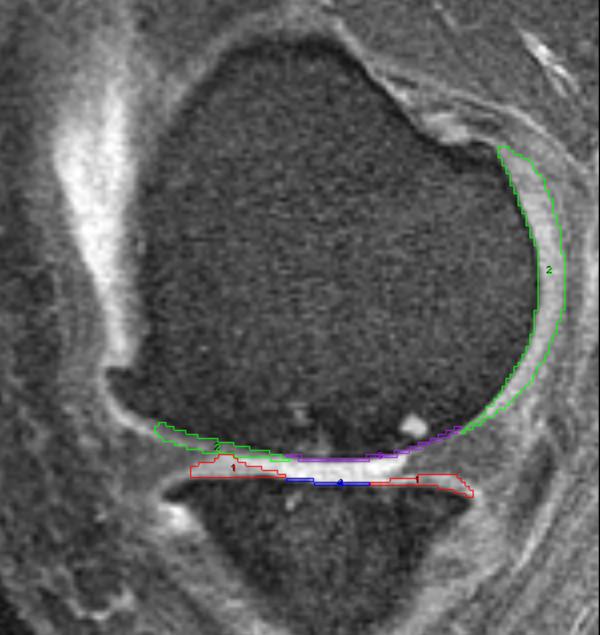

Bone marrow lesions (BMLs), common osteoarthritis-related magnetic resonance imaging findings, are associated with osteoarthritis progression and pain. However, there are no articles describing the use of 3-dimensional quantitative assessments to explore the longitudinal relationship between BMLs and hyaline cartilage loss. The purpose of this study was to assess the cross-sectional and longitudinal descriptive characteristics of BMLs with a simple measurement of approximate BML volume, and describe the cross-sectional and longitudinal relationships between BML size and the extent of hyaline cartilage damage.

107 participants with baseline and 24-month follow-up magnetic resonance images from a clinical trial were included with symptomatic knee osteoarthritis. An 'index' compartment was identified for each knee defined as the tibiofemoral compartment with greater disease severity. Subsequently, each knee was evaluated in four regions: index femur, index tibia, non-index femur, and non-index tibia. Approximate BML volume, the product of three linear measurements, was calculated for each BML within a region. Cartilage parameters in the index tibia and femur were measured based on manual segmentation.

方法

纳入了一项临床试验的基线和 24 个月随访的磁共振图像,共 107 名有症状的膝骨关节炎患者。为每个膝关节确定了一个“索引”关节,定义为疾病严重程度较大的胫股关节。随后,每个膝关节在四个区域进行评估:索引股骨、索引胫骨、非索引股骨和非索引胫骨。每个区域内的每个 BML 计算三个线性测量值的乘积,得出近似 BML 体积。根据手动分割测量索引胫骨和股骨的软骨参数。